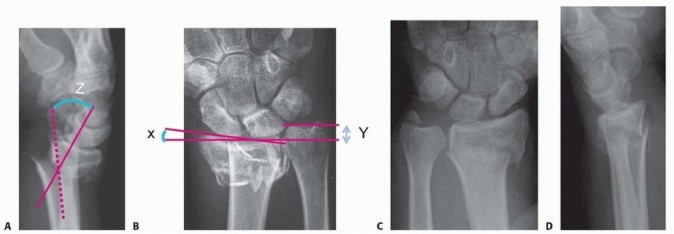

### FIG 2 • A. PA radiograph demonstrating radial inclination

(black lines)

, ulnar variance

(red)

, and radial height

(white bracket)

. B. Lateral radiograph of the wrist demonstrating volar tilt

. Visualize and palpate the hand and fingers for swelling, ecchymosis, tenderness, crepitus, and deformity. Use two-point tool or paper clip bent to 5 mm and touch radial and ulnar aspects of all fingers with one or two points. Greater than normal (5 mm) two-point testing in the form of progressive neurologic deficit may signify an acute or chronic carpal tunnel syndrome.

Posteroanterior (PA), lateral, and oblique radiographic views are critical in evaluating all suspected distal radius fractures. Consider imaging the uninjured wrist for comparison and to serve as a template for surgical reconstruction. Radiographs of the elbow should be obtained in almost all cases, especially if any tenderness, swelling, or deformity is detected clinically. Radiographic measurements taken from the PA view ( FIG 2A) include the following14, 24: Radial inclination, which is the angle between a line perpendicular to the shaft of the radius at the articular margin and a line along the radial articular margin Normal angle: 21 degrees Radial length, which is the distance from a line tangential to the ulnar articular margin to a line drawn perpendicular to the long axis of the radius at the radial styloid tip Normal length 4: 9 to 11 mm Ulnar variance, which is the distance from a line perpendicular to the long axis of the radius at the sigmoid notch and a line tangential to the ulnar articular surface Normal length 4: 0 mm Lateral articular (volar) tilt is the angle between a line for the articular surface of the radius and a perpendicular line to the long axis of the radius. Normal angle: 11 degrees volar tilt ( FIG 2B)4, 14, 24 Computed tomography (CT) scans can fully elucidate the anatomy of the fracture, particularly articular disruption or incongruity. They also help to determine the necessary surgical approach by defining the location and extent of comminution. CT scans increase the interobserver reliability of treatment plans and may actually alter the initial treatment plan based on plain radiographs. 7